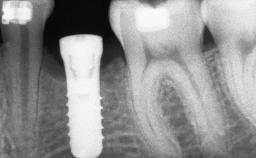

A 45-year-old woman with a completely edentulous maxilla was referred to evaluate the possibility of rehabilitation with an implant-supported prosthesis. This patient was healthy and a non-smoker. She had been wearing a maxillary complete denture opposing a natural mandibular dentition since her twenties. This situation had resulted in progressive resorption of the alveolar ridge, repeatedly creating a need for relining the denture. Twenty years later, despite multiple adaptations and the use of “glues” the denture was unstable and causing the patient psychological and functional discomfort.

| # of Implants | 8 |

| Bone Augmentation | Horizontal|Sinus Floor Elevation|Staged|Vertical |

| Augmentation Materials | Autogenous chips|Autogenous block(s) |